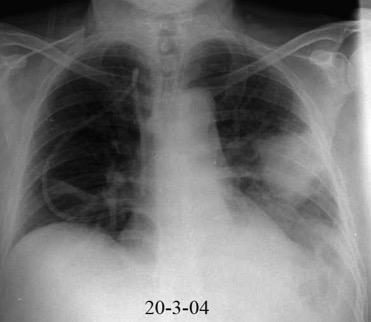

Neumonía a neumococos base izda. con derrame que aumenta.

Broncograma en lateral y en US.

(36-66% en ingresados)